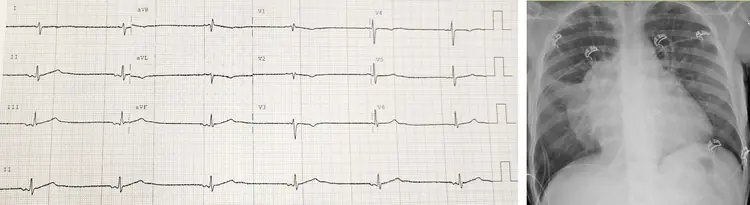

Un ragazzo di 20 anni accede al Pronto Soccorso di un ospedale spoke per recente comparsa di dispnea a riposo (“New York Heart Association” IV). Interrogato, riferisce astenia e tosse secca da circa due mesi. Dal raccordo anamnestico si evince un’abitudine tabagica attiva ed un’obesità di primo grad